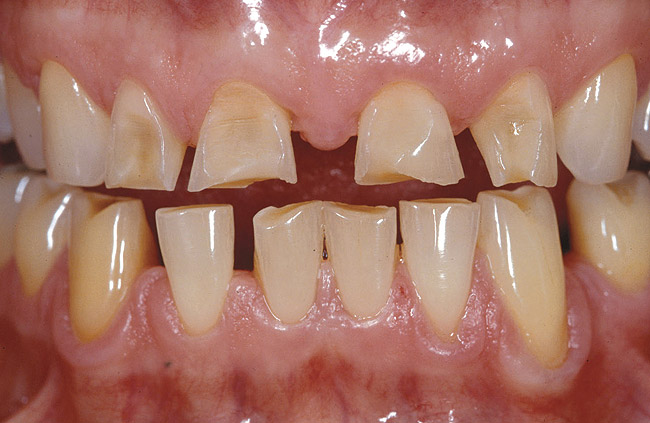

Figure 1b  Preoperative view showing a severe case  of localized erosion and wear with marked and multiple dentin exposures. Such a case is definitely not a contraindication for a conservative approach with bonded porcelain restorations with a facial veneer type IIIB, provided that dentin exposures are sealed immediately after tooth preparation.

Figure 1b

• i>Maximum tooth structure preservation. When used on full-crown coverage preparations and combined with glass ionomer or modified-resin cements, IDS can result in significantly increased retention, exceeding the cohesive strength of the tooth.29 IDS can therefore constitute a useful tool for improving retention when dealing with short clinical crowns and excessively tapered preparations. Provided that optimal adhesion is achieved also at the inner restoration surface (eg, porcelain etching and silanization, as in the case of inlays, onlays, and veneers), traditional principles of tooth preparation can be omitted and significantly more conservative tooth structure removal is enabled (Figure 1).30

The first technical step for the application of IDS is the identification of exposed dentin surfaces. A simple but efficient method is to proceed to a short etching (2 to 3 seconds) and thorough drying of the prepared surfaces. Dentin can be easily recognized because of its glossy aspect, whereas enamel is frosty. It goes without saying that after this initial etch, the dentin surface must be reprepared (eg, a slight roughening with a diamond bur) to expose a fresh layer of dentin and re-etched before the application of the DBA.

As mentioned earlier, DBA thicknesses can reach several hundred micrometers when applied to concave areas.19 When using IDS, the additional adhesive layer can sometimes negatively affect the thickness of the future restoration. This is particularly evident in the case of porcelain veneers and in the presence of gingival margins in dentin (Figure 2). When margins terminate in dentin, a marked chamfer (0.7 mm to 0.8 mm) is recommended to provide adequate margin definition and enough space for the adhesive and overlaying restoration (Figures 2A through 2C). A shallow chamfer would cause the adhesive resin to pull over the margin and compromise both margin definition and porcelain thickness.9 In other axial locations, confined and superficial dentin exposure gives only a limited space for the restorative materials, including the bonding agent. The application and curing of the DBA would significantly reduce the space left for the ceramic buildup. Considering that a low ratio of ceramic to luting agent thickness can negatively influence the stress distribution within the porcelain,32,33 IDS is not indicated for very superficial dentin exposures. On the other hand, deeper preparation surfaces (ie, in the presence of Class IV or V defects or in the case of inlay/onlay/overlay preparations) can be easily treated with IDS before impression taking because sufficient space is left for the restorative material to maintain a reasonable ratio of thicknesses between the ceramic and the luting agent.